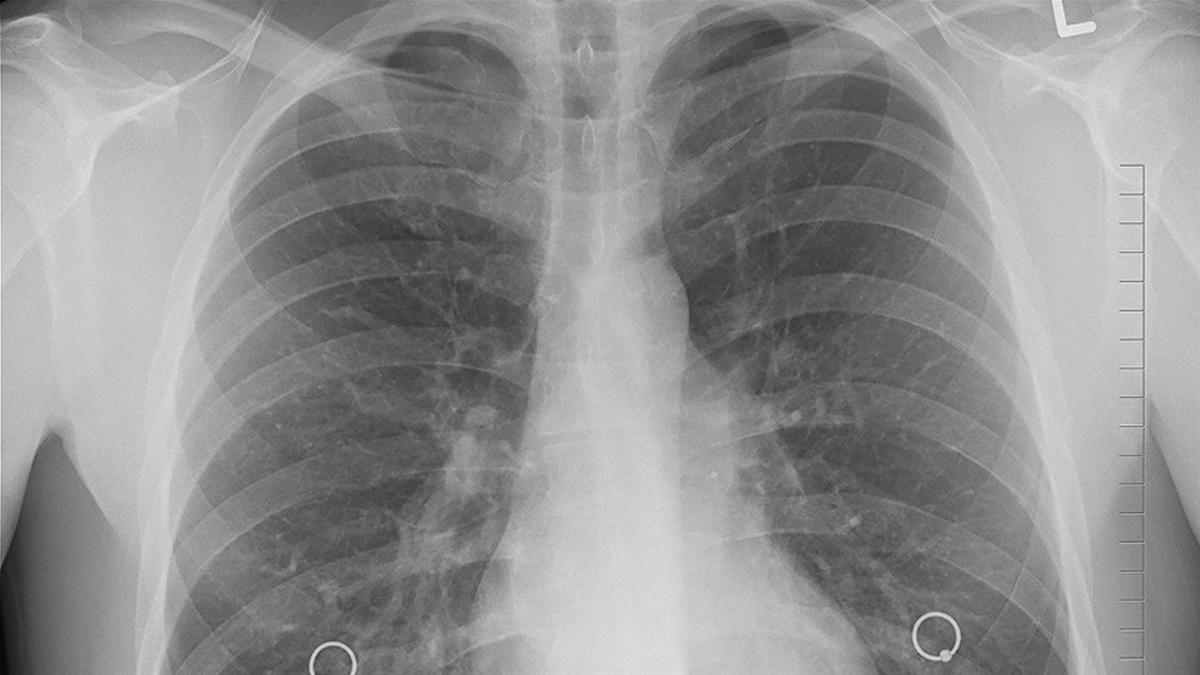

Gizli tehlike: Sigara içmeyenlerde akciğer kanseri neden artıyor?

Northwestern Medicine'daki araştırmacılar, akciğer kanseri hastalarının yüzde 65'inin mevcut tarama kılavuzlarına göre uygun olmadığını ortaya koydular. Özellikle kadınlar, Asyalı Amerikalılar ve hiç sigara içmemiş kişilerin erken teşhis imkanından mahrum kaldığı bulundu.

Akciğer kanseri teşhisinin geç aşamalarda konulması, hastalığın tedavi edilebilirliğini önemli ölçüde azaltıyor. Northwestern Medicine'de yürütülen yeni bir çalışma, bu sorunun kökeninde mevcut tarama kılavuzlarının yetersizliğinin yattığını gösteriyor. Araştırma sonuçlarına göre, akciğer kanseri hastalarının yaklaşık üçte ikisi, resmi tarama önerilerine uymadıkları için erken teşhis fırsatından yoksun kalıyor.